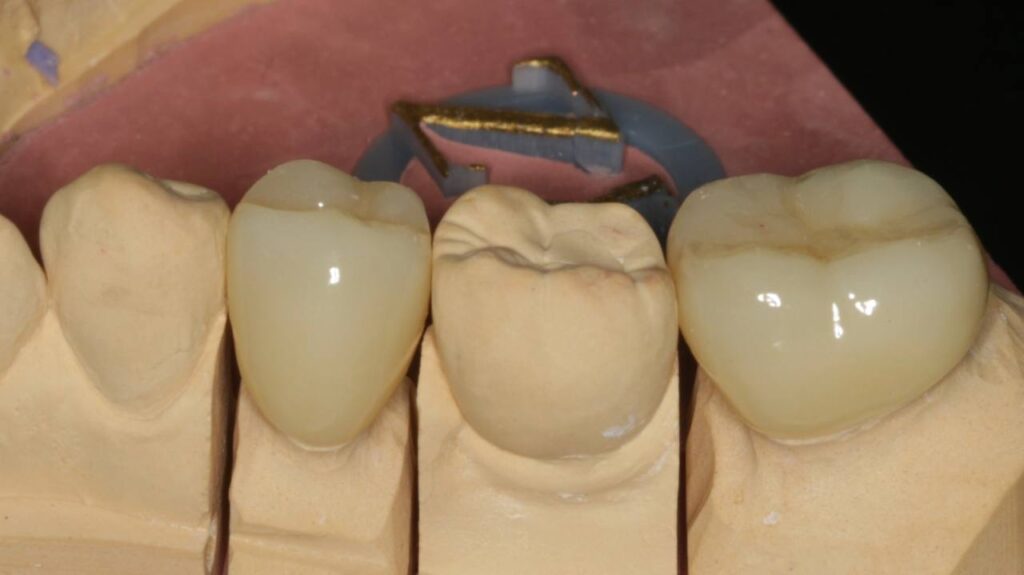

Протезирование коронками из диоксида циркония, после эндодонтического лечения — Исламов Л.А.(01.04.2026)